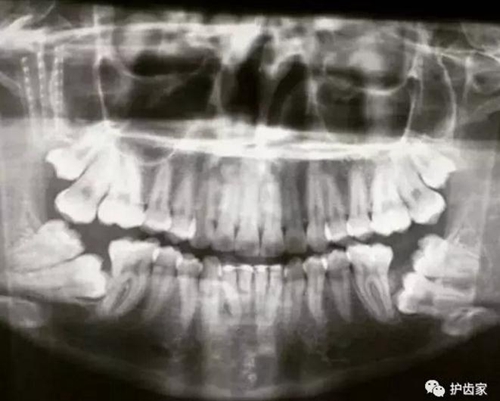

拍片是為了了解智齒周圍情況,也是為了了解智齒結(jié)構(gòu),牙根結(jié)構(gòu)千變?nèi)f化,有可能是融合成一個(gè)根,也可能是八爪根。不同牙根不同位置及方向,只有通過拍片來確認(rèn)。

拍片也為了了解下頜神經(jīng)與智齒的關(guān)系,一般離得近,有醫(yī)療風(fēng)險(xiǎn)的,基本沒有醫(yī)生愿意拔,現(xiàn)在沒人為了幾百元,賠上自己的職業(yè)生涯。誰都怕拔智齒,敲打智齒,一不小心,碰到神經(jīng),就攤上大事了。有理都說不清。

通過拍片可以了解牙齒本身:生長方向,牙根數(shù)目,牙根是否彎曲,膨大等。

與重要解剖結(jié)構(gòu)的位置關(guān)系:如上頜磨牙與上頜竇的關(guān)系;下頜磨牙與下頜神經(jīng)管的關(guān)系;兒童在混合牙列期恒牙與乳牙胚的關(guān)系等。可以減少拔牙的風(fēng)險(xiǎn)。

預(yù)知其他病變:如頜骨內(nèi)有無埋伏牙,多生牙,囊腫等。